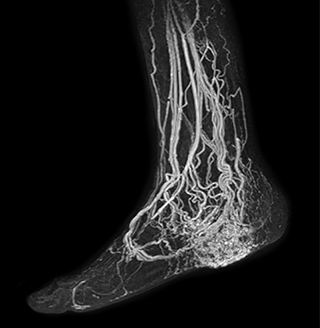

MRA run-off study with mDIXON

The subtractionless peripheral MR angiography shows improved vessel-to-background contrast and high resolution. Ingenia Ambition 1.5T.

Station

Ingenia Ambition

Pelvis

Voxels 1.3 x 1.3 x 3.2 mm, FOV 430 mm, 125 slices

Upper legs

Lower legs

Voxels 1.0 x 0.82 x 2.0 mm, FOV 430 mm, 125 slices

Another example is the foot examination for diabetic patients, which has improved dramatically. “The forefoot is generally difficult to image with MRI because of the inhomogeneities that the toes create – it’s hard to obtain good fat saturation in that area. Here, mDIXON made a huge difference right away, we obtain much better image quality,” Dr. Peña says. “Using mDIXON, Compressed SENSE and the dS FootAnkle coil, we have been able to reduce the scan time, so that we can now also include an additional 3D STIR sequence to visualize both arteries and veins in the foot.”

Avila adds: “In addition, since most of these patients are in a significant amount of pain, it’s important to perform the examination as quickly as possible. With Compressed SENSE and mDIXON we have been able to reduce the scan time from about 45 minutes to just 15 minutes. Not only does this improve patient comfort, we see that it also helps us acquire images without motion artifacts, which is critical to making a confident diagnosis.”